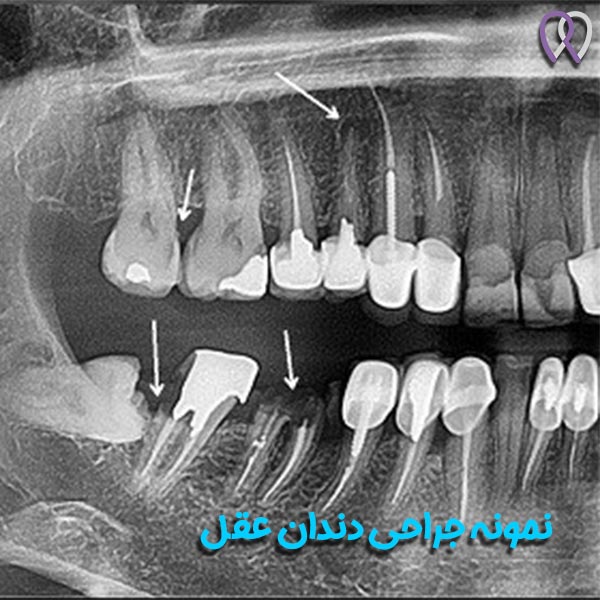

دندان عقل در انتهای فک شما قرار دارد و در سنین بعد از بلوغ کامل یعنی 18 سالگی در می آید ، اما امکان دارد که زودتر یا دیر تر این اتفاق رخ دهد. این دندان ها چهار عدد هستند که یک جفت در فک بالا و جفت دیگر در فک پایین قرار دارند. جراحی این دندان نیز پروسه ای است که در آن دندان ها را خارج می نمایند ؛ زیرا در برخی موارد ممکن است برای این دندان ها مشکلی پیش بیاید مثلا فضای کافی نداشته باشند یا باعث ایجاد درد شوند که با کشیدن دندان عقل می توان این مشکلات را برطرف کرد. همچنین کمبود فضا می تواند جلوی رشد دندان عقل را بگیرد که منجر به درد ، عفونت و سایر مشکلات دهان و دندان می شود. در نتیجه برای درمان مشکلات ناشی از آن باید آن را بکشید. البته در برخی موارد نیز اکثر دندانپزشکان و متخصصین از جمله بهترین دندانپزشک تهران ، دکتر روزبه روزبیانی می گویند در صورت ایجاد نشدن مشکل خاص بهتر است آن را به حال خود رها کنید و نیازی به انجام پروسه خاصی ندارید.

همانطور که شاید بدانید این دندان ها آخرین دندان های آسیاب و ثابت هستند که در دهان شما رشد می نمایند. این دندان ها معمولا در سنین بین 17 الی 25 سال رشد می نمایند. در برخی افراد این دندان ها هرگز رشد نمی کنند و در برخی نیز به طور طبیعی آغاز به رشد می نمایند. همچنین در بعضی از موارد نیز باعث مشکل می شوند و با تجویز بهترین دندانپزشک تهران ، شما را نیازمند به انجام جراحی دندان عقل می کنند. این دندان ها می توانند دچار مشکلات زیر شوند :

- با زاویه ای به سمت دندان آسیاب جلوی خود رشد نمایند و به آن آسیب بزنند

- با زاویه ای به سمت عقب دهان یعنی لثه رشد نمایند

- زاویه راستی داشته باشد که به سمت دندان دیگر رشد کند به اصطلاح در دندان فک دراز بکشد

- به درستی به سمت بالا یا پایین رشد نماید اما همواره در استخوان فک گیر بیافتد